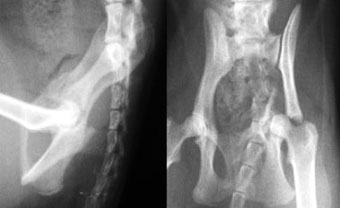

体重11kgの犬。

左側腸骨と坐骨で骨折していました。

腸骨はプレート法で、坐骨はプレート法とピンニングの併用で整復固定しました。

写真上段: 手術前

骨盤の一部が割れて内側に変位しています。

写真下段: 手術後 |